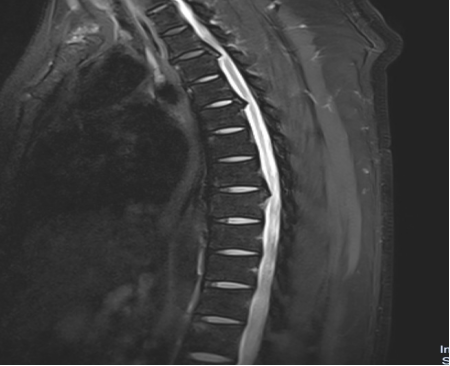

入院后,國文醫(yī)院骨科迅速組織多名專家會診,并為吳先生完善了頸椎及胸椎的 MRI 檢查。結果顯示,吳先生的頸椎及胸椎多階段嚴重椎管狹窄,脊髓壓迫超過 50%,情況十分危急。經過骨科專家團隊的綜合會診及評估,最終為他制定了一套個性化的治療方案,包括頸椎后路單開門椎管減壓頸椎融合內固定術,以及胸椎間盤切除伴椎管減壓胸椎植骨融合內固定術。在完善術前檢查、確認無手術禁忌后,骨科主任呂國福如期為吳先生實施了手術。

手術涉及頸椎及胸椎多個階段,操作難度極大。專家團隊采用 “蠶食法” 減壓,分塊去除增生韌帶,最大程度減少對脊髓的損傷;同時運用椎弓根螺釘固定技術,確保手術部位的穩(wěn)定性。